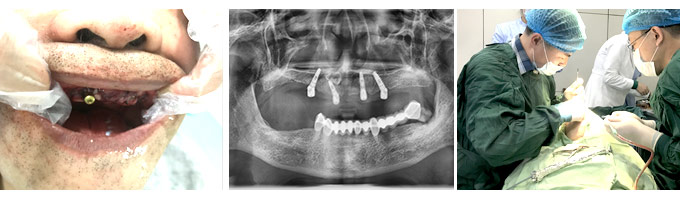

牙齿种植

Dental implants

缺失了一颗牙一定要尽早的进行修复治疗,以免造成周围的牙齿也跟着出现松动和脱落。种植牙的价格 一直是大家比较关注的,那么,无锡种一颗牙价格是多少?

种植牙

无锡康贝佳口腔医生介绍说,种植牙的费用没有一个固定的数字,影响种植牙费用的因素有很多,具体 有以下几点: